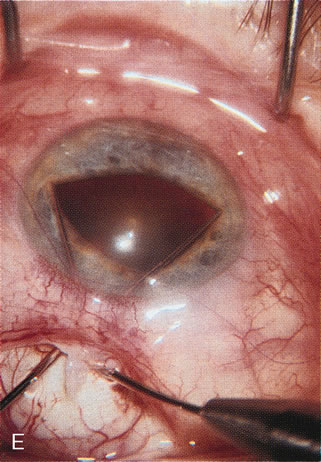

Fig. 4. Viscocanalostomy with deep sclerectomy and phacoemulsification. Nonpenetrating filtration procedures (NPFS) may be combined with phacoemulsification. Patients with mild disc damage and a history of limited topical drug therapy are the best candidates. Patients who require an IOP in the low teens are not good candidates for NPFS. By definition, NPFS is designed to lower IOP without penetrating into the anterior chamber, thereby avoiding the complications associated with trabeculectomy. Viscocanalostomy is intended to allow aqueous to percolate through a trabeculodescemetic membrane into a subscleral cavern created by the deep sclerectomy. The aqueous diffuses from the cavern into the dilated ostia of Schlemm's canal and into the episcleral venous plexus. A. Fashion a uniform 300-micron superficial scleral flap 1 mm into clear cornea. B. Construct a second 600-micron deep flap that facilitates the unroofing of Schlemm's canal, seen as the darker area. C. Use viscoelastic to dilate the ostia of Schlemm's canal. The major problem with viscocanalostomy is the eventual closure of the ostium decreasing flow to the episcleral plexus. D. Dissect the deep flap anteriorly into clear cornea creating the trabeculodescemetic membrane. This membrane is clearly seen between the scleral spur and the bend of the deep flap. The integrity of this membrane ensures the nonpenetrating portion of the surgery. Another problem with NPFS is the eventual fibrosis of this initially transparent membrane requiring goniopuncture. E. Deep sclerectomy gets its name from removal of the deep flap. Removal of this flap creates the potential subscleral space for accumulation of aqueous before it enters Schlemm's canal and exits the episcleral venous plexus. After removal of the deep flap, the superficial flap is sutured into place and conjunctiva closed. Approximately half of these procedures develop a shallow bleb.